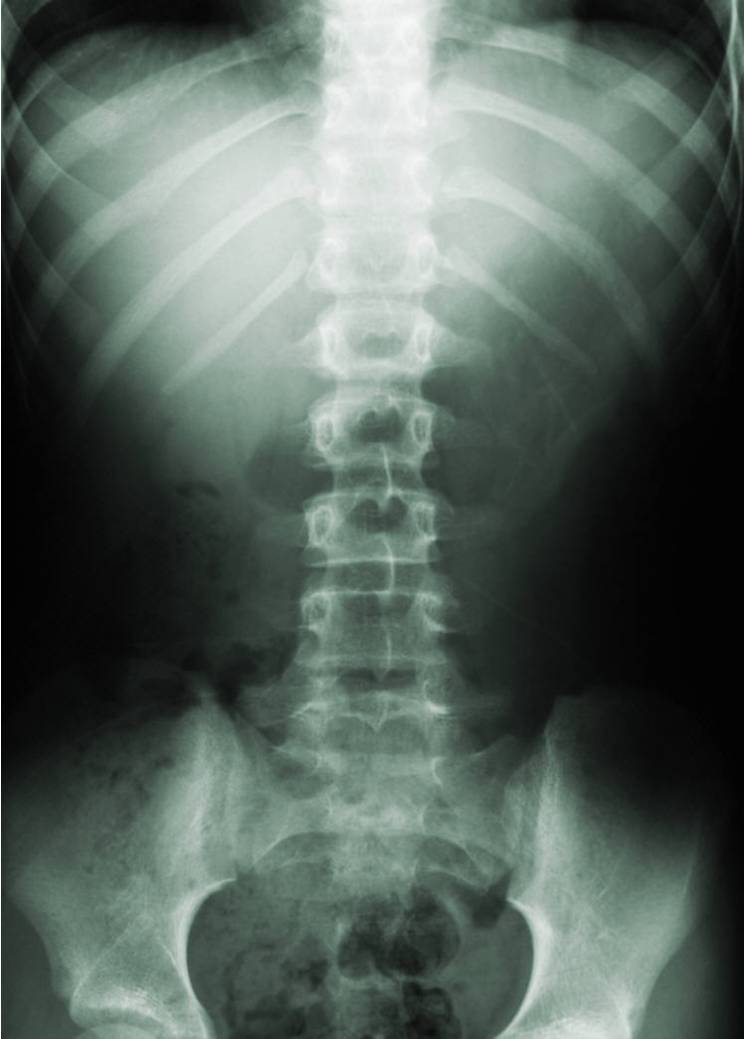

A: Your chiropractor will examine your spine, your posture, and will observe your range of motion. The doctor will also assess how each spinal joint is moving in order to determine where problems may be in your spine. In addition to this different orthopedic tests may be done to rule in or rule out a certain diagnosis. Additionally, x-rays of your spine will be taken to get a picture of your vertebrae and see first hand if there are more serious problems that only an x-ray may show.

A: Your chiropractor will examine your spine and through a series of different orthopedic tests and x-rays will evaluate whether or not your pain is originating from misalignments in your spinal column. Your chiropractor, after 4 years of graduate school, is specifically trained to locate and identify your cause of back pain and to properly treat and eliminate it either through chiropractic care or through referral to another health care provider if needed. After careful examination, your chiropractor will perform a spinal adjustment to correct misaligned vertebrae.

Your chiropractor will view an x-ray of your spine to rule out serous conditions and to check alignment.

There are natural curves that should be present in your spine. Your chiropractor will inform you if these are present or if you have an abnormal curve.